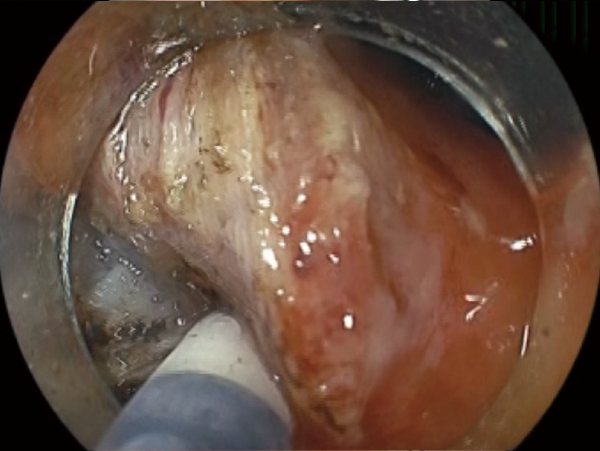

Clinical Image :Marking

Clinical Image :Water jet

Clinical Image :Mucosal Injection

Clinical Image :Submucosal dissection

Clinical Image :Submocosal injection

Clinical Image :Coagulation